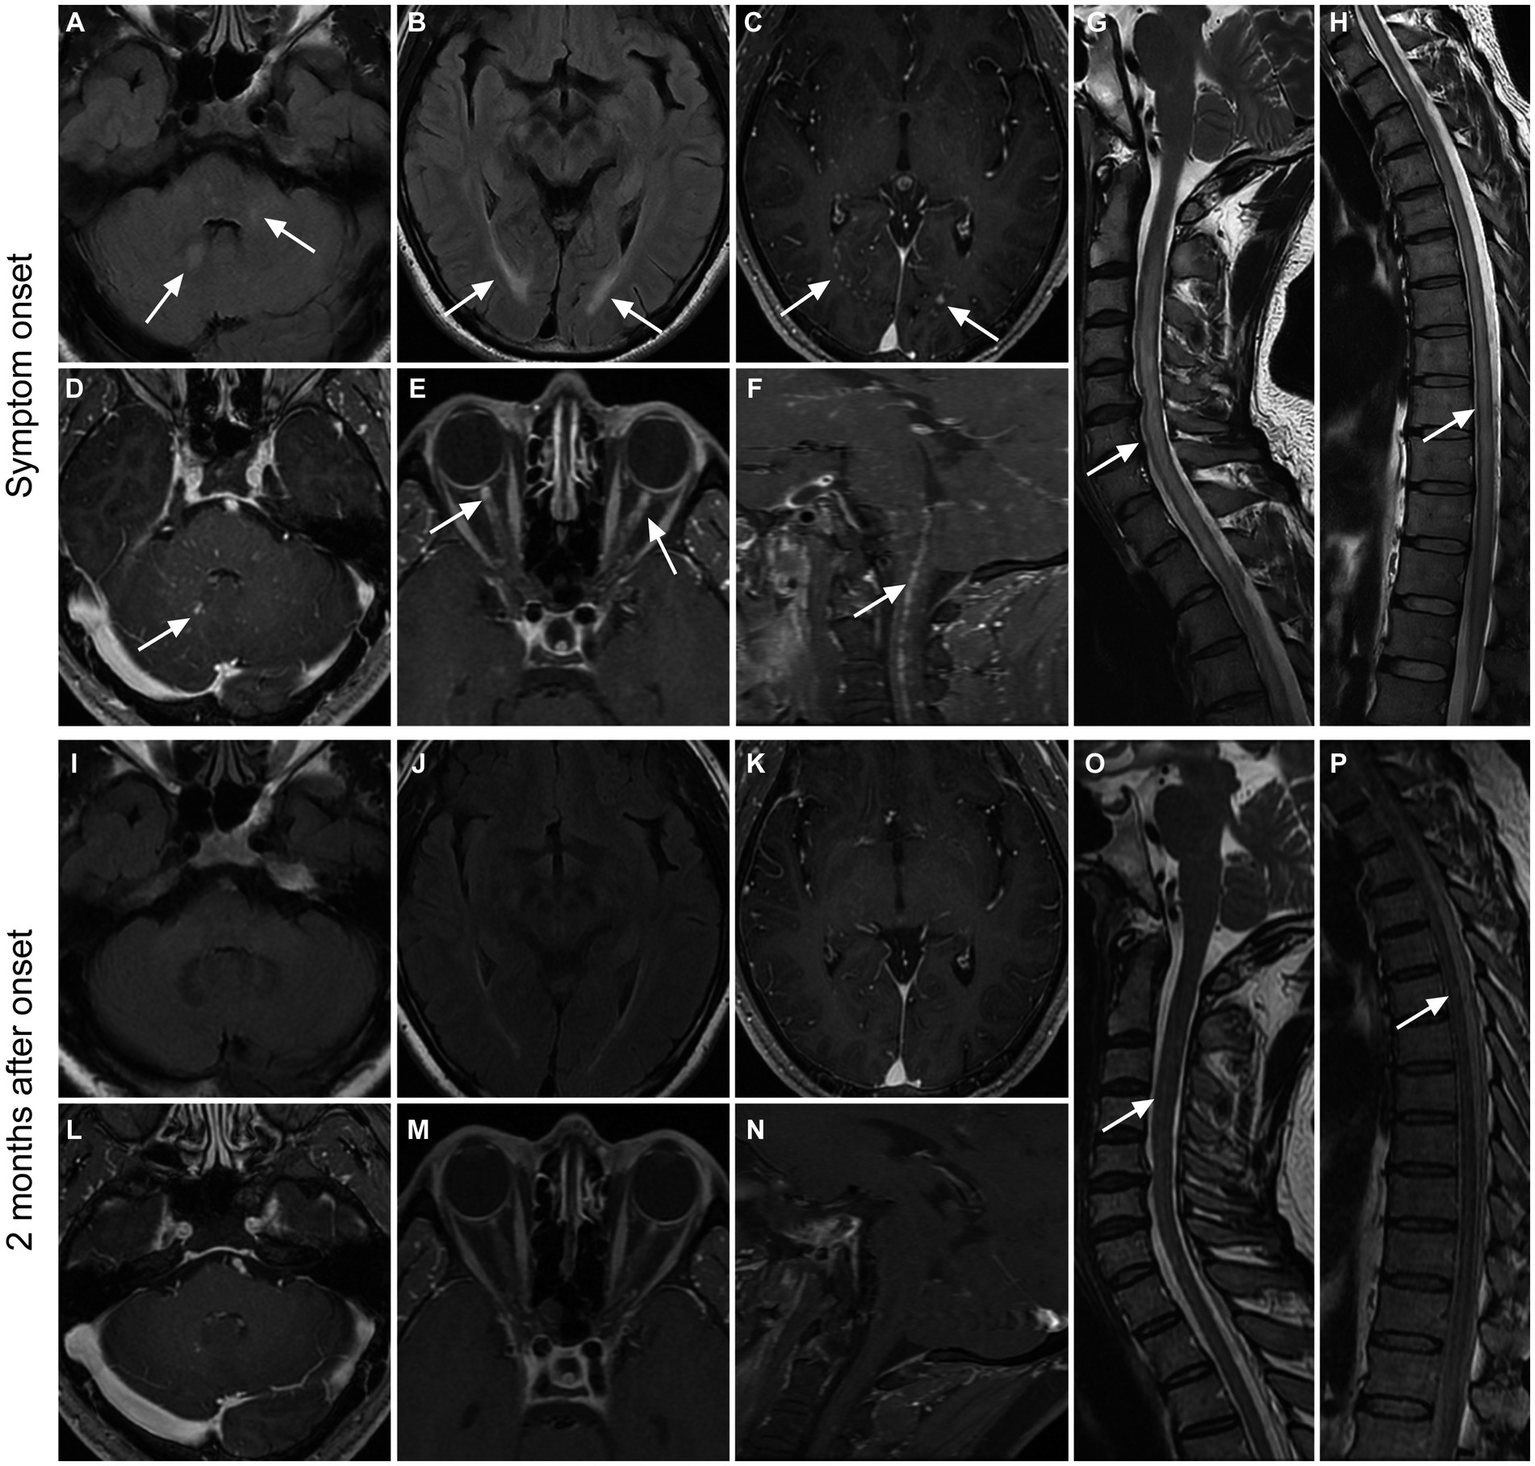

Thirteen patients received imaging follow-up, with a median follow-up time of 46 days (range: 11–477 days). As shown in Table 5; Figure 2, 7 of 11 patients (63.6%) had decreased cerebral parenchymal lesions, while 3 of 4 patients (75%) had decreased cerebral parenchymal enhancement. In addition, meningeal enhancement decreased in all 4 cases (100%), and perivascular radiation enhancement decreased in all 3 cases (100%). Spinal cord lesions decreased in all 7 cases (100%), with 5 cases (100%) showing decreased spinal cord lesion enhancement. Additionally, meningeal and central canal enhancement was reduced or disappeared in all 4 cases (100%). For optic nerve lesions, 2 cases (100%) had a decrease in size, and 1 case (100%) had a decrease in both optic nerve lesions and sheath enhancement.

Figure 2

Imaging findings in a patient with GFAP. A 36-year-old male presented with bilateral lower limb weakness and numbness, accompanied by unsteady gait, with a subacute onset. After treatment with glucocorticoids, intravenous immunoglobulin, and tacrolimus, there was an improvement in symptoms, and a follow-up examination after 2 months showed a mRS score of 1. Initial MRI examination during the onset of the disease (A–H) revealed high T2WI signal in the cerebellar hemisphere and brainstem (A), as well as in the periventricular white matter surrounding the bilateral lateral ventricles (B). Additionally, there were punctate enhancements observed in the periventricular regions surrounding the bilateral lateral ventricles (C, arrows), as well as in the cerebellar hemisphere and brainstem (D, arrow). Furthermore, there was prominent enhancement in the anterior-middle portion of the bilateral optic nerves (E) and linear enhancement in the central canal of the medulla oblongata and cervical spinal cord (F). The cervical spinal cord (G), thoracic cord, and conus medullaris (H) had hyperintensity on T2WI throughout the entire segments. Follow-up MRI examination at 2 months after onset (I–P) showed the disappearance of T2WI hyperintensity and enhanced lesions in the brain parenchyma (I–L). The enhancements in the optic nerves and medulla oblongata-cervical cord central aqueduct disappeared (M,N). Most of the T2-weighted hyperintensity lesions in the spinal cord were resolved (O,P).